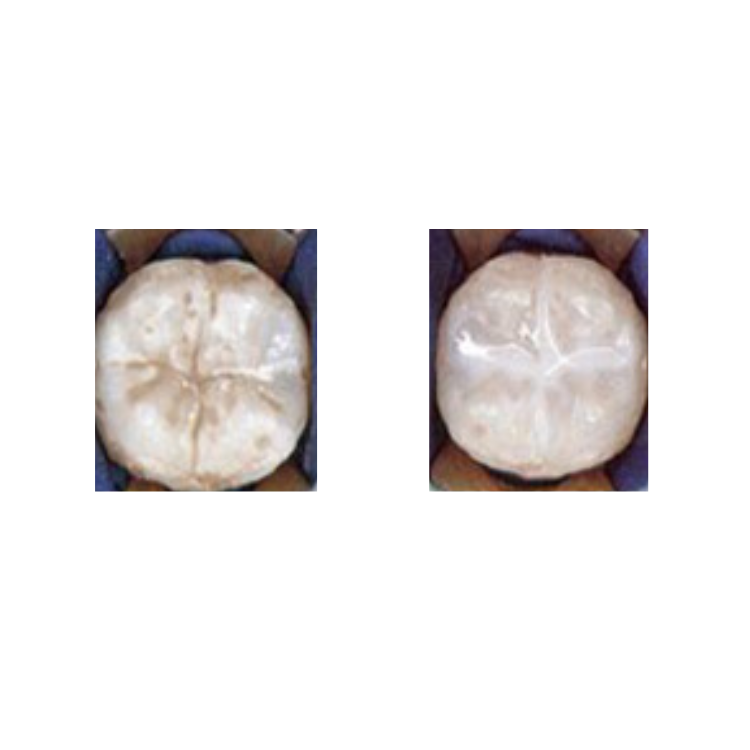

Dental sealants

Sealants are thin, white cement coatings. They seal off the grooves and dips on the top of the teeth. This keeps bacteria and food from getting caught in them and causing cavities. The sealant is placed on top of the tooth.